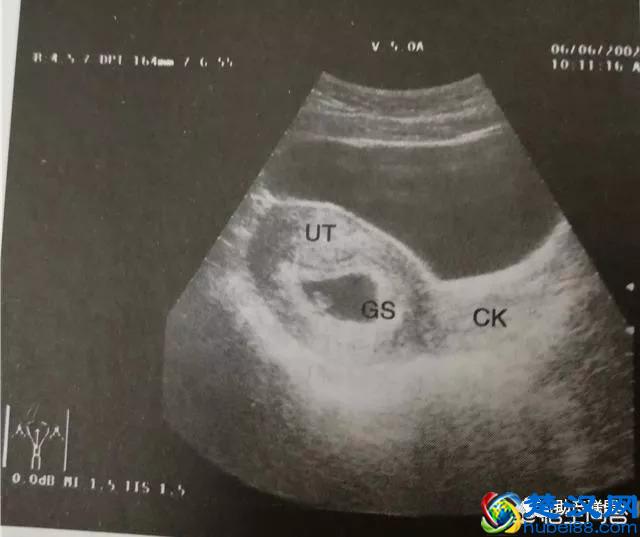

早孕第一步曲 ---胎囊(GS),也就是临床上讲的孕囊(GS),停经35天(5周)时,宫腔内可见到圆形或椭圆形的妊娠囊(孕囊),孕囊是原始的胎盘组织,被羊膜,血管网包裹的小胚胎,是怀孕最初的形态。提示宫内孕,此时孕囊一般占宫腔的1/4。